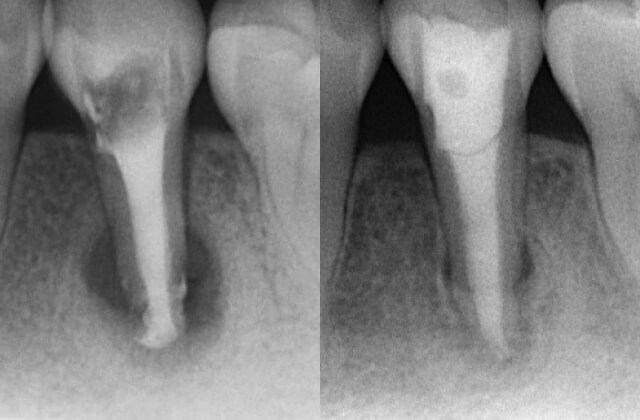

根管治療

当院の根管治療についてご説明致します。